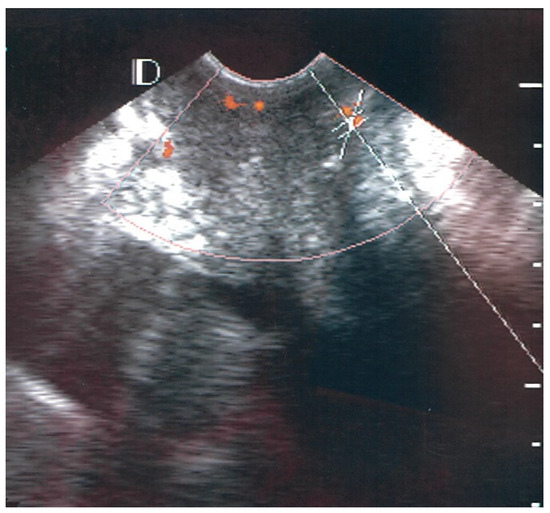

3.1. Visual Classification of Vascularity Findings on TV-PDU

| Classification | Numbers of Visualize Vascular Hotspots within Cervix (One Spot: 1 × 1 mm) |

|---|---|

| Class 0 | 0 |

| Class I | 1 to 5 |

| Class II | 5 to 10 |

| Class III | >10 |